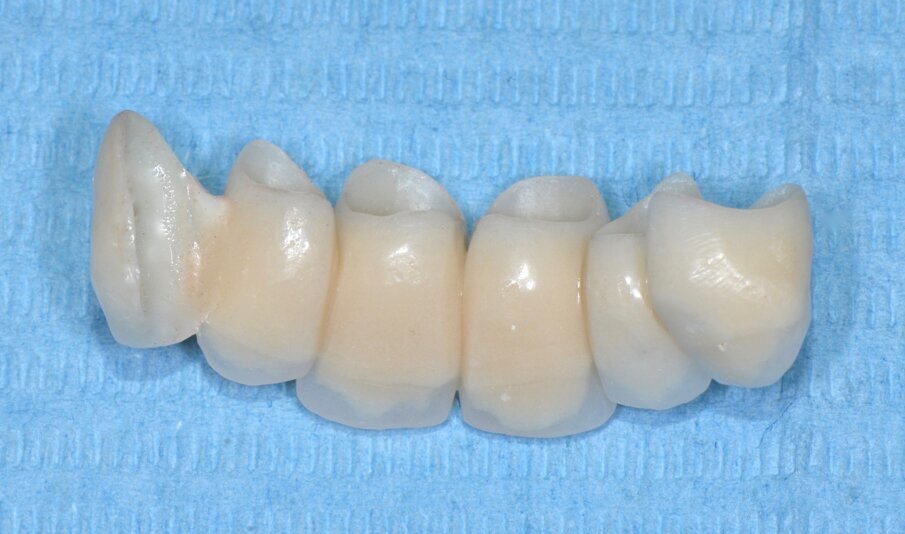

Le corone definitive, come precedentemente descritto, vengono costruite con tecnologia CAD/CAM per una sottostruttura in zirconia di cui viene verificato l’adattamento e ricercata la precisione seguendo gli stessi criteri noti per una prova fusione di una struttura metallica (Figg. 23-29). Dopo la prova le strutture vengono inviate in laboratorio per la stratificazione della ceramica.

La successiva prova clinica è quella delle ceramiche a biscotto durante la quale viene valutata l’occlusione, la fonetica e l’estetica (Figg. 30-33). Durante la stessa seduta viene eseguita la preparazione per la faccetta in disilicato di litio per il canino superiore sinistro che viene rilevata insieme con l’impronta di rimontaggio delle corone superiori. Una faccetta in resina sul canino viene ribasata e solidarizzata al provvisorio superiore (Figg. 34). La settimana successiva i manufatti finiti vengono provati, cementati adesivamente e vengono eseguite le radiografie finali di controllo (Figg. 35-47).